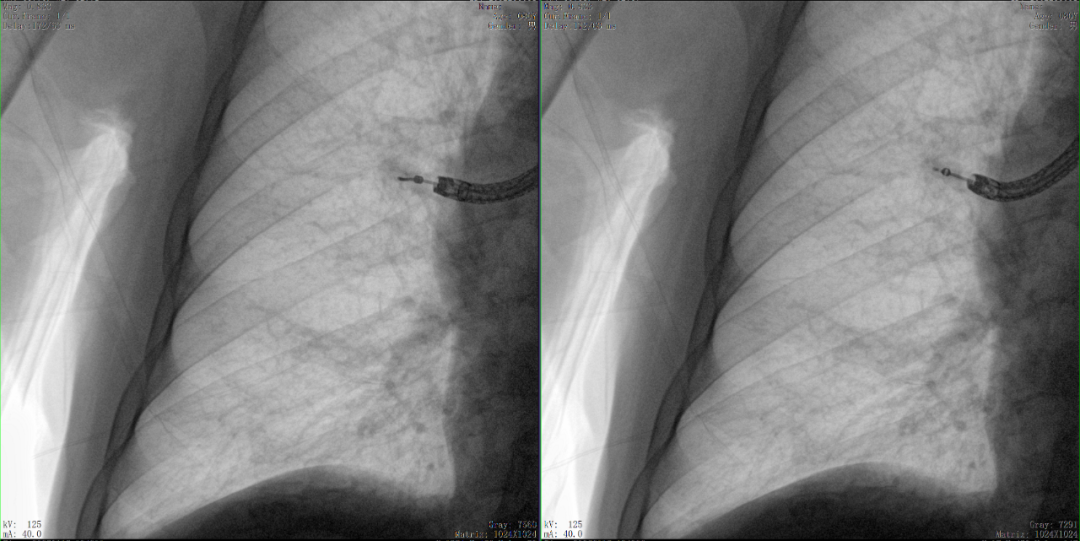

病例3:超聲支氣管鏡下肺活檢(80歲)

三維C形臂還可以創(chuàng)新性地應(yīng)用在呼吸介入領(lǐng)域。例如,在經(jīng)皮穿刺或經(jīng)支氣管鏡肺結(jié)節(jié)活檢、定位、消融等場(chǎng)景中,用于確認(rèn)工具是否到達(dá)病灶、消融范圍是否完全覆蓋病灶等。

二維影像無法準(zhǔn)確判斷工具是否到達(dá)病灶

三維各切面影像都顯示工具達(dá)到病灶內(nèi)